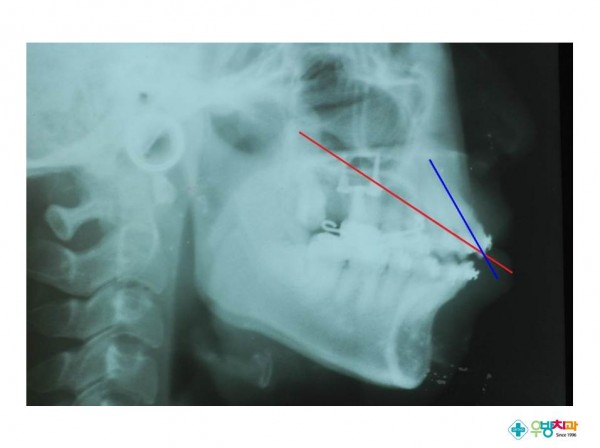

[Gummy smile, protrusion 환자 적용]

Nonextraction treatment with temporary skeletal anchorage devices to correct a Class II Division 2 malocclusion with excessive2.pdf